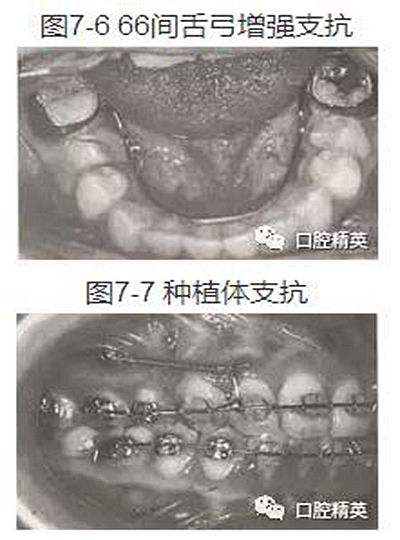

(7)66間加舌弓(圖7-6)。

(8)隨著口腔種植學(xué)的發(fā)展,頜骨內(nèi)種植體己成為口腔正畸治療中的一種支抗手段。種植體支抗的最大特點(diǎn)是可避免以牙齒或牙弓作為支抗結(jié)構(gòu)時(shí)可能出現(xiàn)的移位,保證了矯治過程中對(duì)牙列間隙的完全利用(圖7-7)(詳見第十一章)。